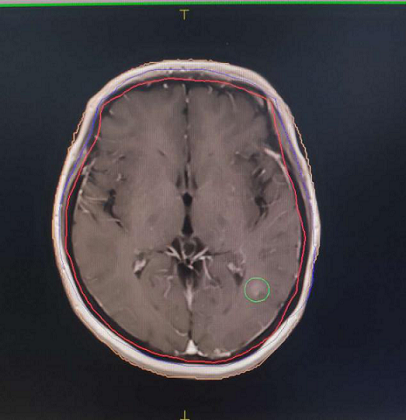

左图为CT图像,右图为图像融合后画面,可以清晰观察到圈内病灶。

在查看患者影像资料后,为进一步提升靶区勾画的精准度,提升放疗疗效,刘冠副主任决定采取CT/MRI图像融合技术为患者进行靶区勾画。在阿克苏第一人民医院放疗科副主任郑光浩、物理师胡东等人的配合下,CT/MRI图像融合技术勾画放疗靶区获成功。

刘冠副主任介绍,为患者制定放疗计划时,需要根据患者影像检查结果来确定肿瘤边界,由于CT与MRI两者的成像原理不同,突出显示的解剖结构也有所不同,但如果通过数据转换,将不同种的影像互相融合在一起,使MRI与CT图像的优势相结合,实现信息互补,便可以精确勾画患者肿瘤区域,为放射治疗方案的确定与临床诊断提供更丰富的信息。此举对精确放射治疗具有重要的研究意义。